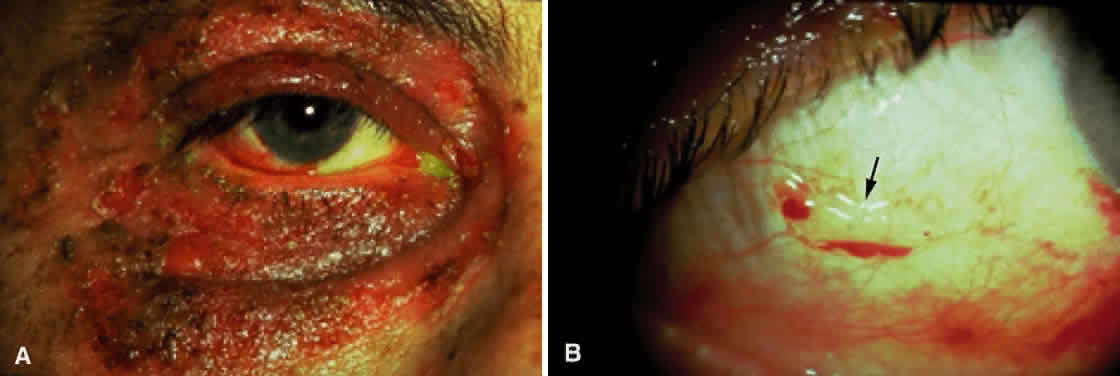

Skin involvement is found less frequently than mucuos membrane involvement (see Table 1) and is reported in 9% to 24% of cases.1–5 The skin lesions of CP may be divided into two types: (1) a recurrent, vesiculobullous, nonscarring eruption that may involve the inguinal area and extremities and occasionally becomes generalized (Fig. 1); and (2) localized, erythematous plaques with overlying vesicles and bullae that appear on the scalp and face near the affected mucous membranes and heal, leaving smooth, atrophic scars (Fig. 2).6

Cicatricial pemphigoid generally runs a chronic course, characterized by progressive shrinkage of the conjunctiva. When the end stage of this disease is reached, the eye lacks tears and has obliterated conjunctival fornices, ankyloblepharon, and a keratinized ocular surface epithelium. Episodes of acute disease activity may interrupt this chronic progressive course and result in rapid shrinkage of the conjunctiva.15 Acute disease activity may be precipitated by surgical procedures, including conjunctival biopsy, lysis of symblepharon, oculoplastic procedures on the eyelids, and cataract extraction. The acute manifestations consist of localized, ulcerated conjunctival mounds (Fig. 4) or diffuse, severe conjunctival hyperemia and edema (Fig. 5). Before concluding that acute inflammatory activity is caused by the disease process, it is necessary to eliminate other confounding factors such as trichiasis, exposure, or bacterial blepharoconjunctivitis.